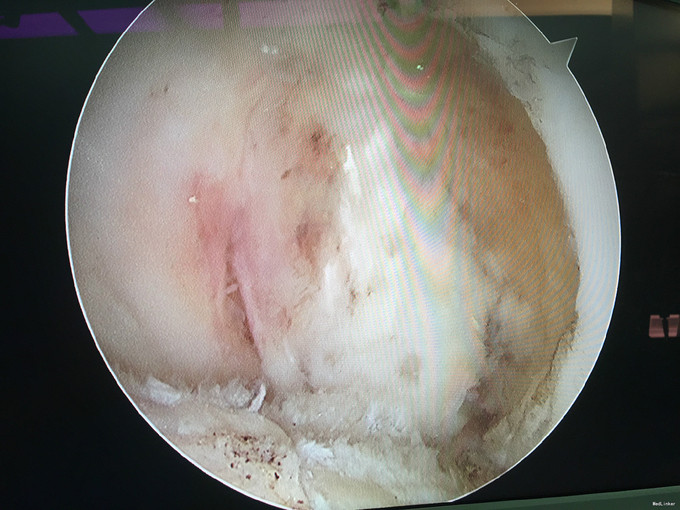

入院诊断:左膝半月板损伤、左膝前交叉韧带损伤 治疗:入院后行左膝关节镜下外侧半月板成形+髁间窝成形+前交叉韧带自体肌腱重建手术。

随访:患者因为病程较长(十余年),术后3月膝关节才恢复正常活动度,行走正常。建议其术后1年再恢复正常运动。 讨论:该病例膝关节损伤时间较长,手术时关节已表现为提早退变(患者年龄并不大)。在前交叉韧带重建前,需要对其狭窄的髁间窝进行成形。术后恢复时间也较一般情况下延长。因此,建议关节出现病损应及时诊治。